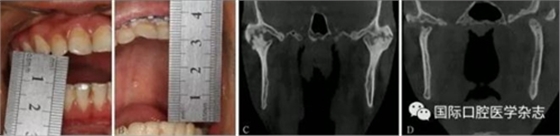

A:術(shù)前開(kāi)口度;B:術(shù)后開(kāi)口度;C:術(shù)前影像學(xué)檢查片;D:術(shù)后影像學(xué)檢查片。

圖 19 關(guān)節(jié)成形術(shù)前后對(duì)比